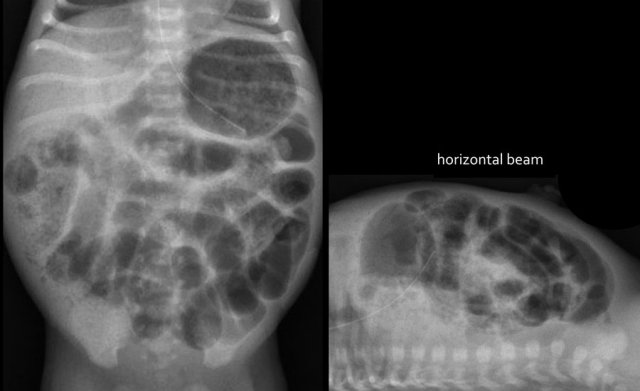

Case 3

Study the image.

What are the findings and what is your diagnosis.

Then scroll through the images for the diagnosis.

The findings are:

- Multiple dilated small bowel loops indicate a low obstruction

- Contrast enema show a small caliber in the rectum, sigmoid and colon descendens

Diagnosis:

Long segment Hirschsprung disease